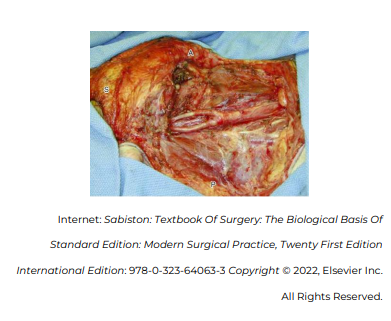

Considerando que a imagem apresenta a visão anatômica do lado direito do pescoço após dissecção radical, no que diz respeito às estruturas visíveis, assinale a alternativa incorreta.